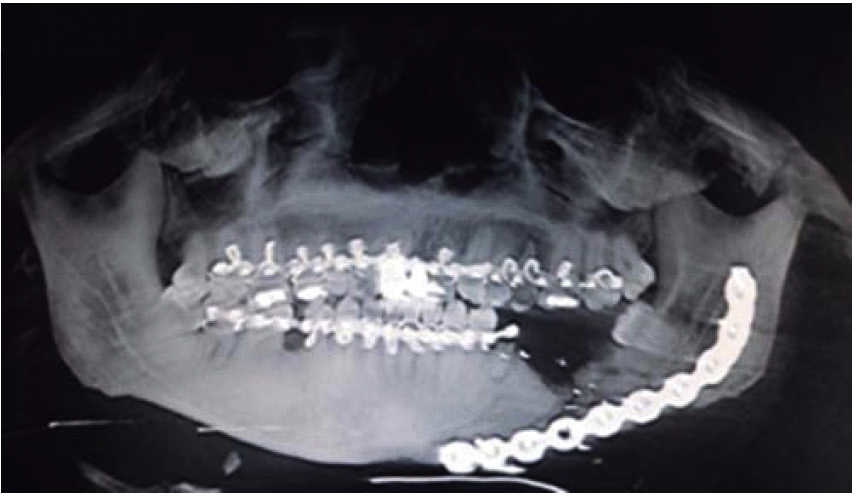

The second surgical event took place seven days later, performing extraoral approach. The fracture was reduced and bone edges were fixated with a 2.4 precontoured mandibular reconstruction plate (Figure 6). Occlusal stability was verified before suturing tissues and bar arches were removed (Figure 7). The patient remained in hospital for seven days, after which he showed suitable occlusion and appropriate healing. Suture points were then removed, a control study was performed and the patient was discharged. The patient did not attend control visits due to the fact that he was incarcerated.

Treatment was initiated with immunization, antibiotic therapy, analgesia, extraction of septic foci and mechanical cleansing of the wound. The patient lacked removable or partial prostheses, so in order to establish inter-maxillary relationship and facial height, gunning splints were manufactured in order to establish inter-maxillary relationship (Figure 13). After ten days of initial treatment, the patient exhibited suitable alveolar healing, with presence of non-fetid secretion at the level of the mandibular wound. The second procedure was then undertaken with extra-oral approach; a 2.4 mandibular reconstruction plate and a 2.0 bone segment plate were used (Figures 14 and 15). The patient was discharged, and she attended periodic assessment visits which showed suitable healing (Figure 16) and adequate mandibular mobility. Three weeks after reconstruction, the patient was instructed to initiate prosthetic treatment in order to achieve rehabilitation.